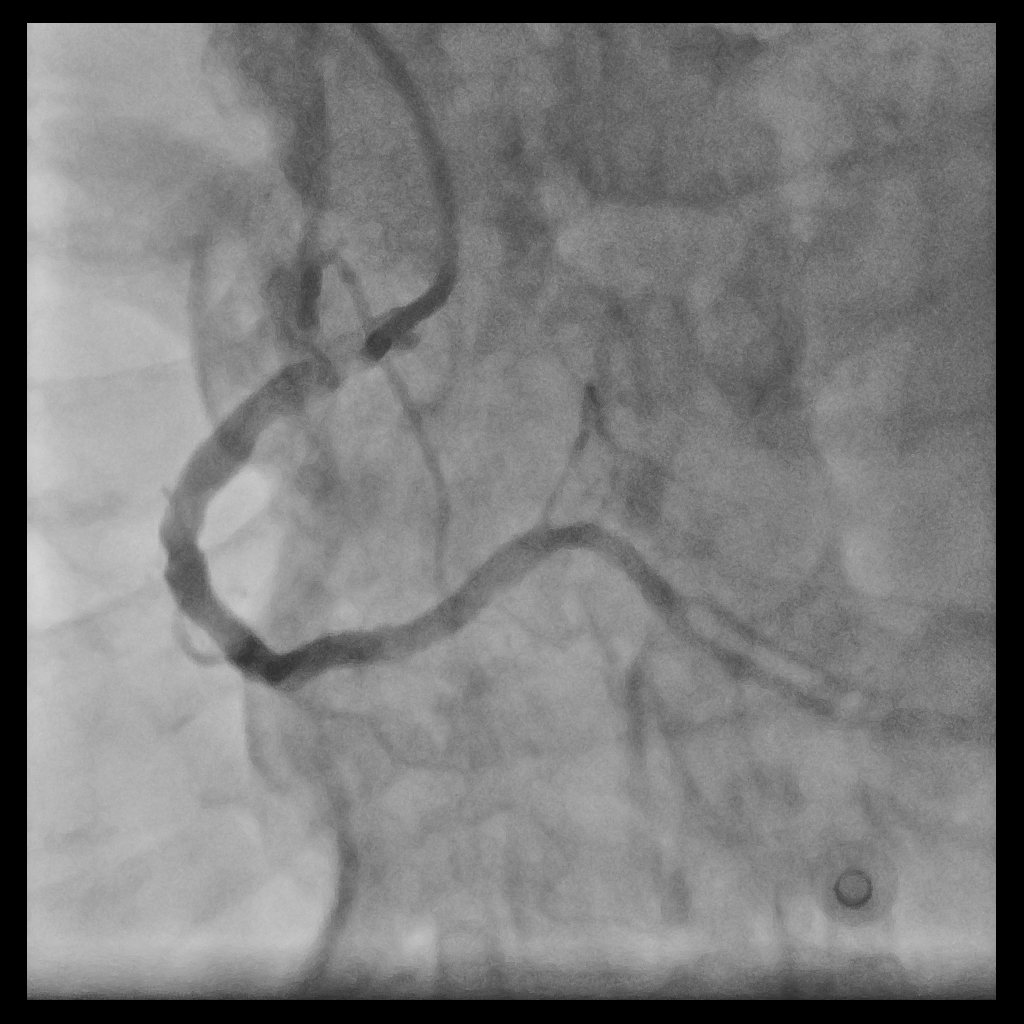

Using an AL1 guiding catheter, we navigated to the RCA-PDA. We performed balloon dilatation of the lesions in the RCA-M to RCA-D. IVUS with manual pullback revealed fibrous plaques with lipid pools and a glimpse of circumferential calcification in the RCA-M. We positioned the Spider FX embolic protection device with its filter basket in the RCA-D. Lesion preparation was done with a Euphora 3.5x30mm balloon. Stent deployment involved deep seating and using a guide extension catheter (GEC) to deploy an Ultimaster-Nagomi 3.5x44mm stent from RCA-M to RCA-D and another Ultimaster-Nagomi stent in the RCA-M. Notable underexpansion was observed in the middle part of the RCA-M stent . Post-dilatation was performed with an NC Accuforce 4.0x15mm balloon at 28 ATM. However, the RCA-M remained non-dilatable with persistent stent underexpansion. IVUS confirmed extensive circumferential calcification in the RCA-M. Despite multiple attempts using the GEC and balloon anchoring technique, we couldn't retrieve the Spider catheter's basket. We then used an intravascular lithotripsy balloon to deliver shockwaves to the proximal calcium ring, alternating with NC balloon inflations. Fortunately this inch-worm advance of the IVL achieved full stent expansion. Eventually, using an anchor balloon with GEC, we successfully retrieved the filter basket. The final angiography showed TIMI-3 flow in the RCA without any hemodynamic change throughout the procedure. A small emboli was found in the filter basket.

Case Summary